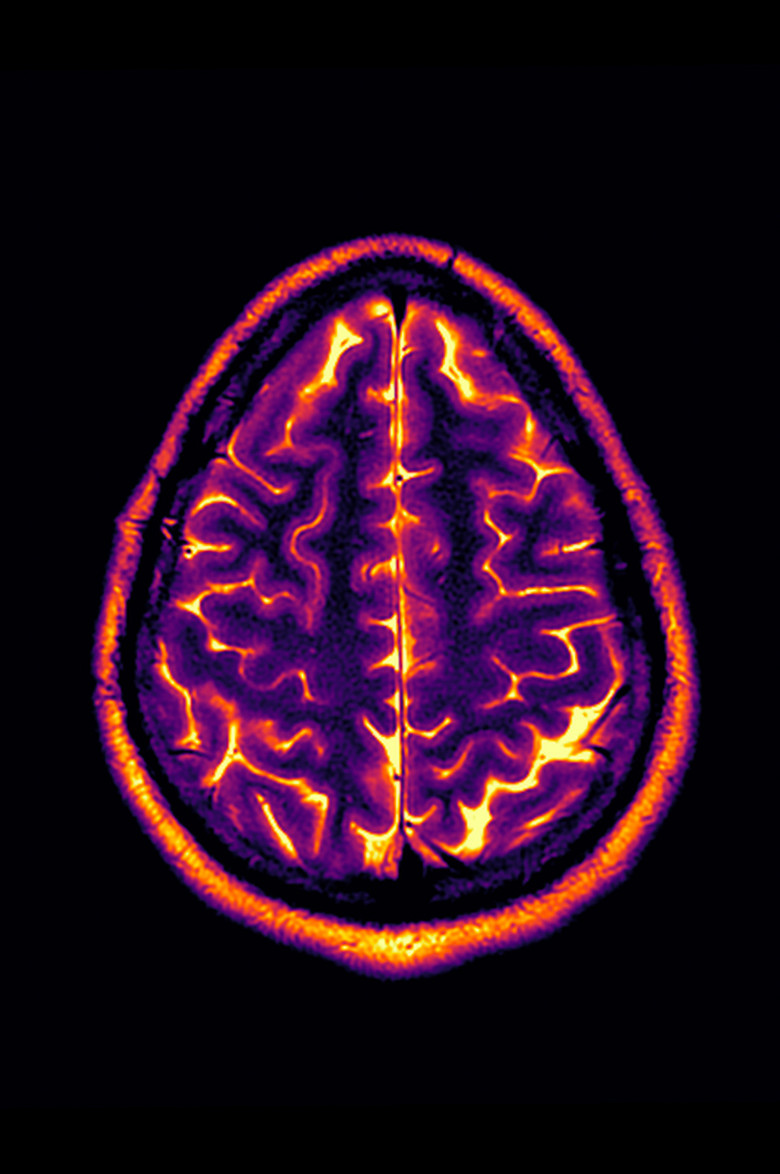

Living with a progressive disease like multiple sclerosis means annual tests and doctor’s visits, and with that comes the usual anxiety about whether this will be the year. Conclusion: Stable Disease is an experimental video made from the artist’s personal MRI image scans from 2018-2022